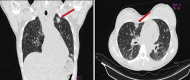

Patient concerns: A 31-year-old woman from California, United States (US), was admitted to the emergency room with a history of 2 days of fever and severe throbbing pain in the left cervical region. Thorax and neck CT tomography revealed confluent cavities suggestive of septic embolism in the lungs and a filiform thrombus in the lumen of the left internal jugular vein, with moderate swelling of the soft and muscular tissues. Methicillin-resistant Staphylococcus aureus (MRSA) was isolated from the blood culture.

Diagnosis: The thrombus in the internal jugular vein associated with cellulitis in the neck and multiple cavitary lesions in the lungs support the diagnosis of LLS caused by MRSA with septic embolization.